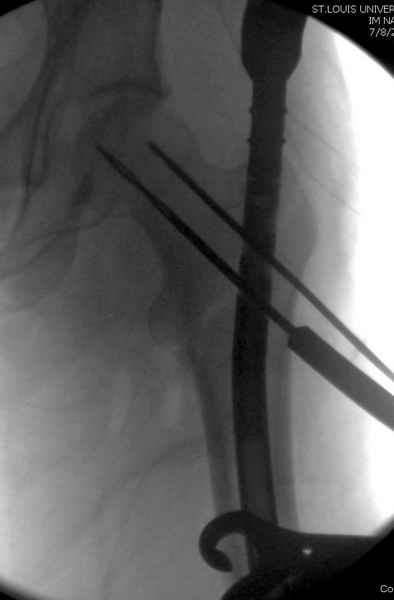

Как раз недавно у меня был примерный случай: больному 36 лет, поступил ночью, травма в результате мотоциклетной аварии, кроме чрезвертельного и спирального перелома левого бедра имеется переломы костей предплечья с этой же стороны. Скелетное вытяжение, а на следующий день больной про оперирован на ортопедическом столе с дистракцией. Чтобы не расколоть чрезвертельный перелом провели временную спицу ближе к переднему кортексу, из малого разреза костодержатель для репозиции, а фиксацию провели антиградным штифтом. Этапы операции на снимках.

Джолдас Кульджанов

DK> фиксацию провели антеградным штифтом.

Да, сейчас это и у нас самый напрашивающийся выбор. Сделали гвоздем ChM, картинки в приложении.